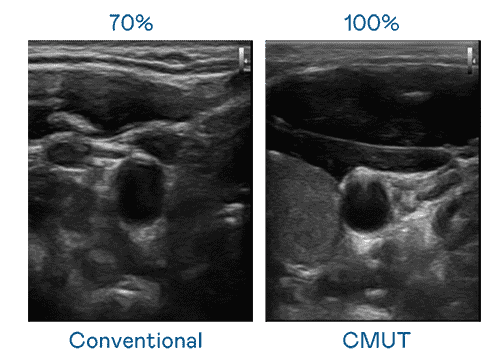

CMUT 技术是一种用电容式微机电元件来产生超音波讯号的技术。。。与传统 PZT 压电式技术相比,,CMUT 频宽增加 30%,,,,更宽频的超音波讯号让影像解析度大幅提升,,,是实现高影像品质医疗超音波扫描、、促进精准医疗发展的关键技术。。

大频宽带来超清晰影像

超音波影像的解析度高低,,,首先取决于探头能发出的讯号频宽。。尊时凯龙 CMUT 可提供高清晰的超音波讯号,,,,提供高频宽、、高灵敏度、、、、影像纹理细节更高的超音波影像,,协助医护人员缩短影像判读时间及利用精准的医疗影像进行诊断。。。